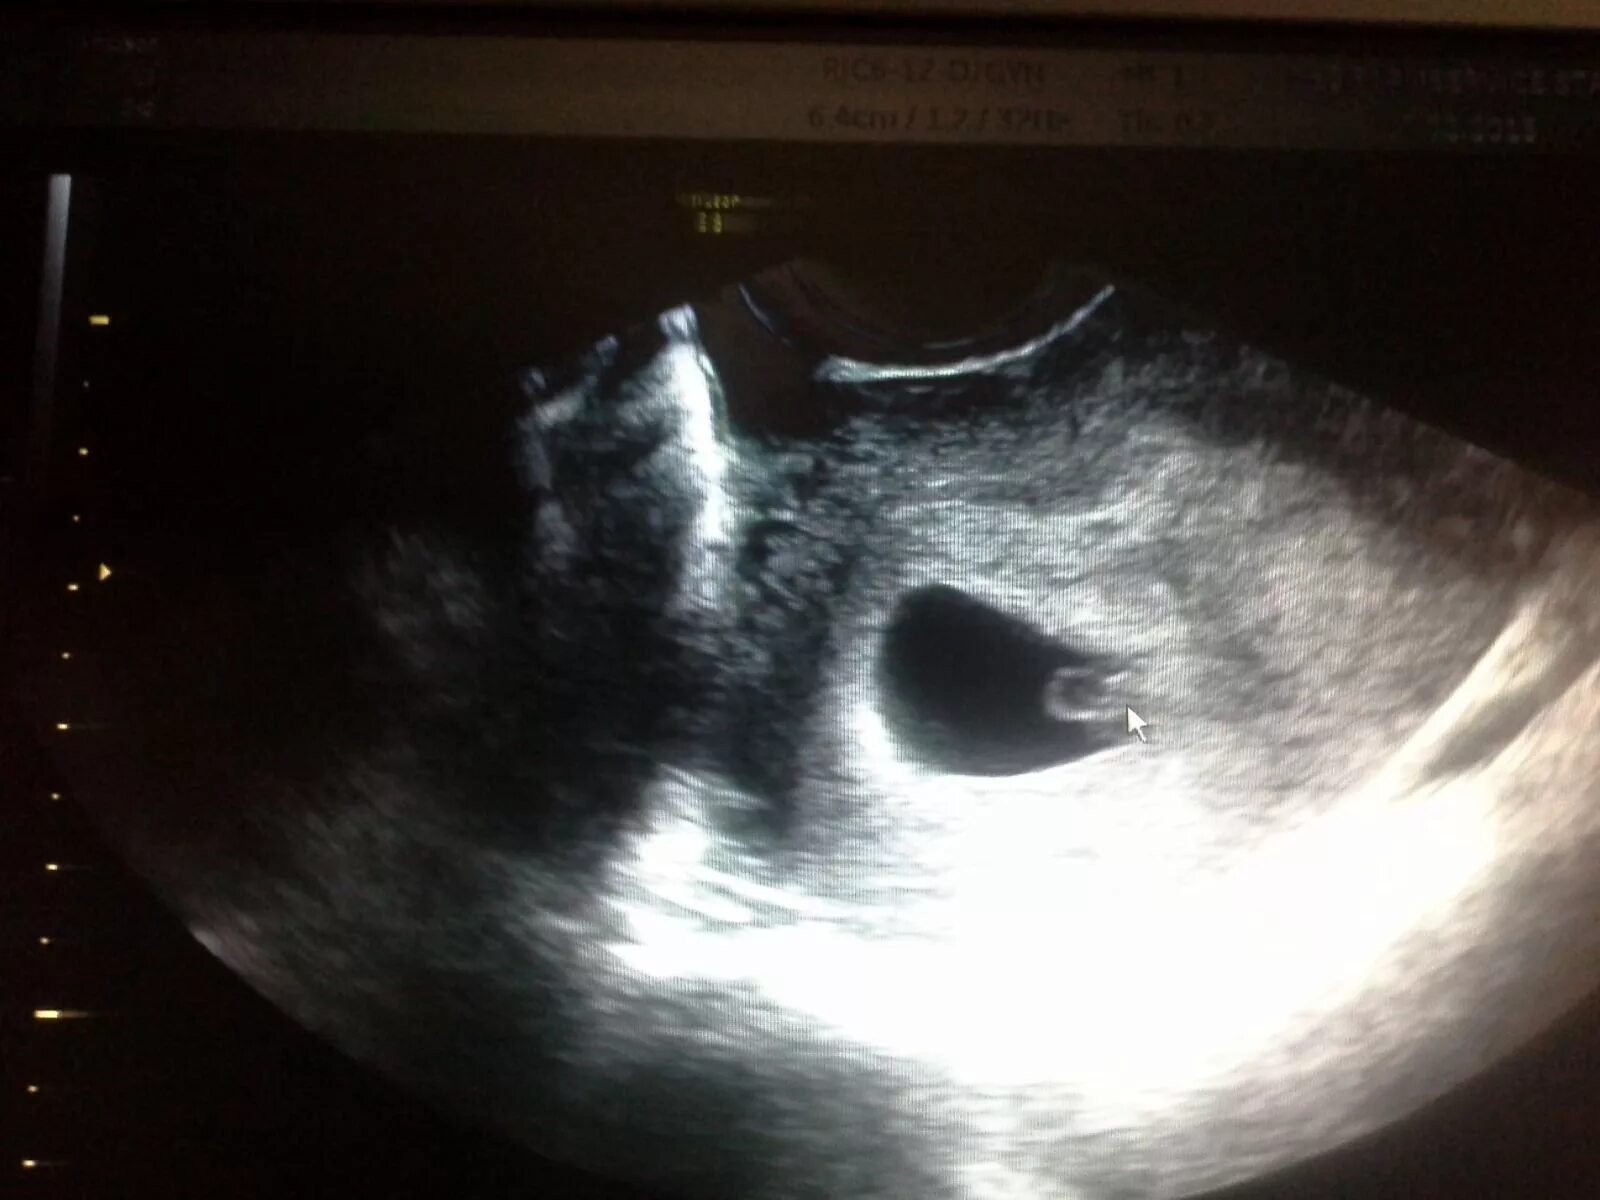

Плодное яйцо 3 мм